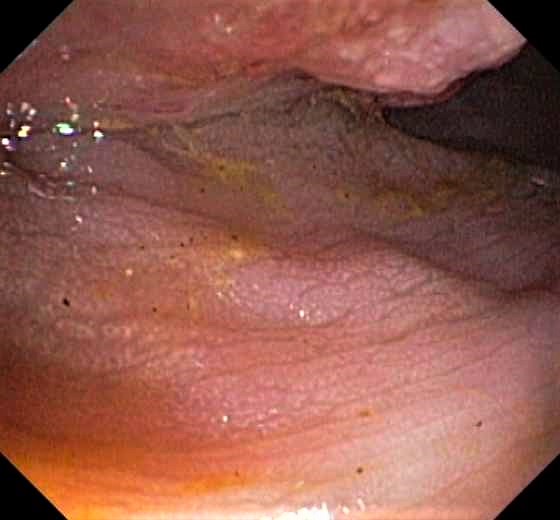

Colon Cancer (Adenocarcinoma) with Chicken Skin Mucosa

Slight Mucosal Changes are frequently seen adjacent to a colorectal cancer or adenoma. First described by Shatz BA et al, they are called Chicken Skin Mucosa (CMS), and are supposed to occur as a result of fat accumulation in macrophages in the lamina propria adjacent to colonic neoplasms. In a series of 852 consecutive colonoscopies CMS was found adjacent to eight of 10 distal colorectal cancers, one of four of proximal colon cancers and 16 of 42 distal adenomas.